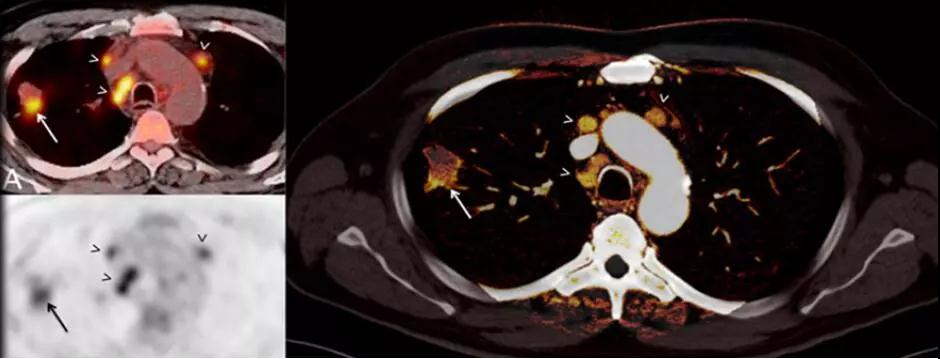

7. 類PET 成像:

傳統(tǒng)PET成像存在輻射劑量過高、放射污染、價(jià)格昂貴等局限性。

SOMATOMForce的純譜雙能量成像技術(shù)具有更好的靈敏度和特異性,使CT雙能量的應(yīng)用上升到一個(gè)前所未有的水平,應(yīng)用范圍更廣泛,不但可以常規(guī)對(duì)腫瘤組織類型、心血管疾病進(jìn)行更為精確的識(shí)別,更是突破影像界限,首次實(shí)現(xiàn)碘、鈣、水、脂肪、鐵等多物質(zhì)多元素多參數(shù)量化成像,能夠精準(zhǔn)評(píng)估骨髓挫傷水腫、腫瘤浸潤(rùn)活性。

△提高診斷準(zhǔn)確性-肺結(jié)節(jié)能量碘圖